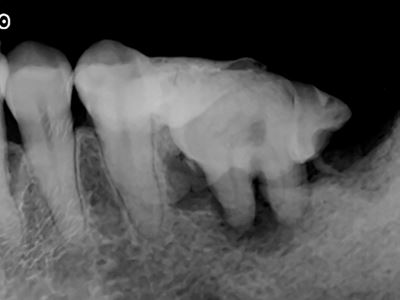

自家歯牙移植用レプリカ症例2-4

X線にて移植床形成量を確認